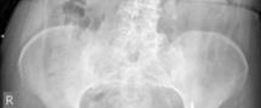

Tibial shaft fracture extending into the plafond—plate fixation Case description A 26-year-old man fell from …